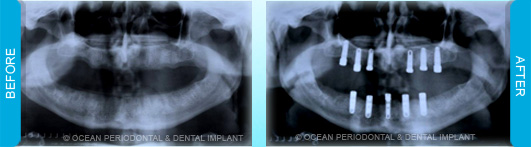

Dental implants are commonly used to replace missing or lost teeth in order to ensure patient comfort, function, and aesthetics. Indeed, there are many treatment options for management of missing teeth, such as bridges, and partial/complete dentures.

Nonetheless, numerous studies have demonstrated that implant-supported restorations are generally deemed to have superior functional and aesthetic outcomes. Furthermore, there are cases where dental implants may be the only logical choice for the restoration of function and aesthetics.